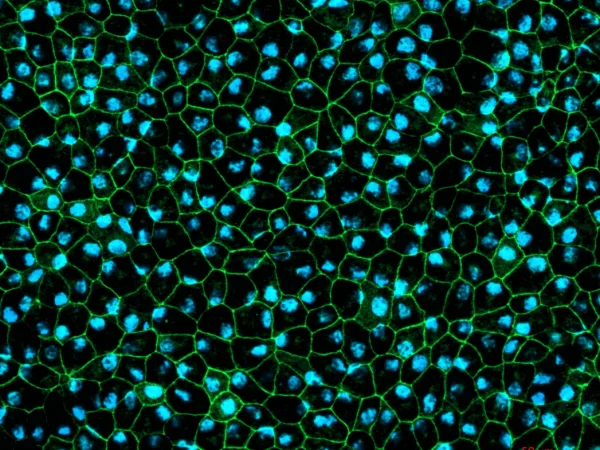

Retinal pigment epithelium (RPE)

RPE cells displaying cobblestone morphology. Cells were immunolabeled with a tight-junction ZO-1 marker (shown in green) and co-stained with nuclei marker Hoechst (shown in blue). Image Credit: Newcells Biotech

A functional monolayer in vitro model of retinal pigment epithelial cells derived from human iPSCs replicates the phagocytosis of photoreceptor outer segments. The pigmented RPE cells have a cobblestone morphology.